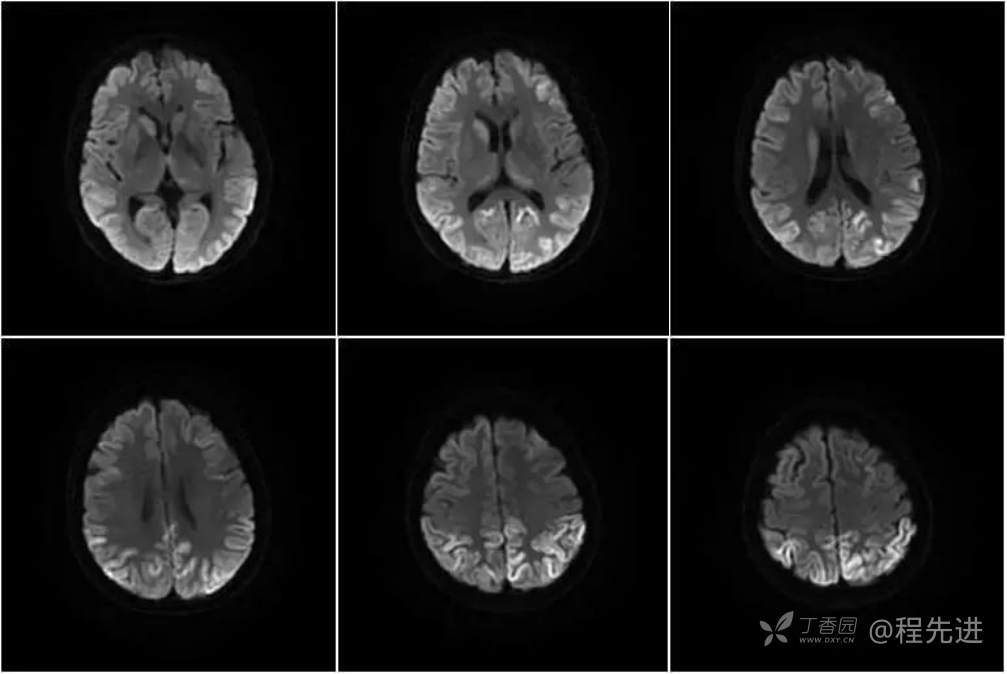

DWI